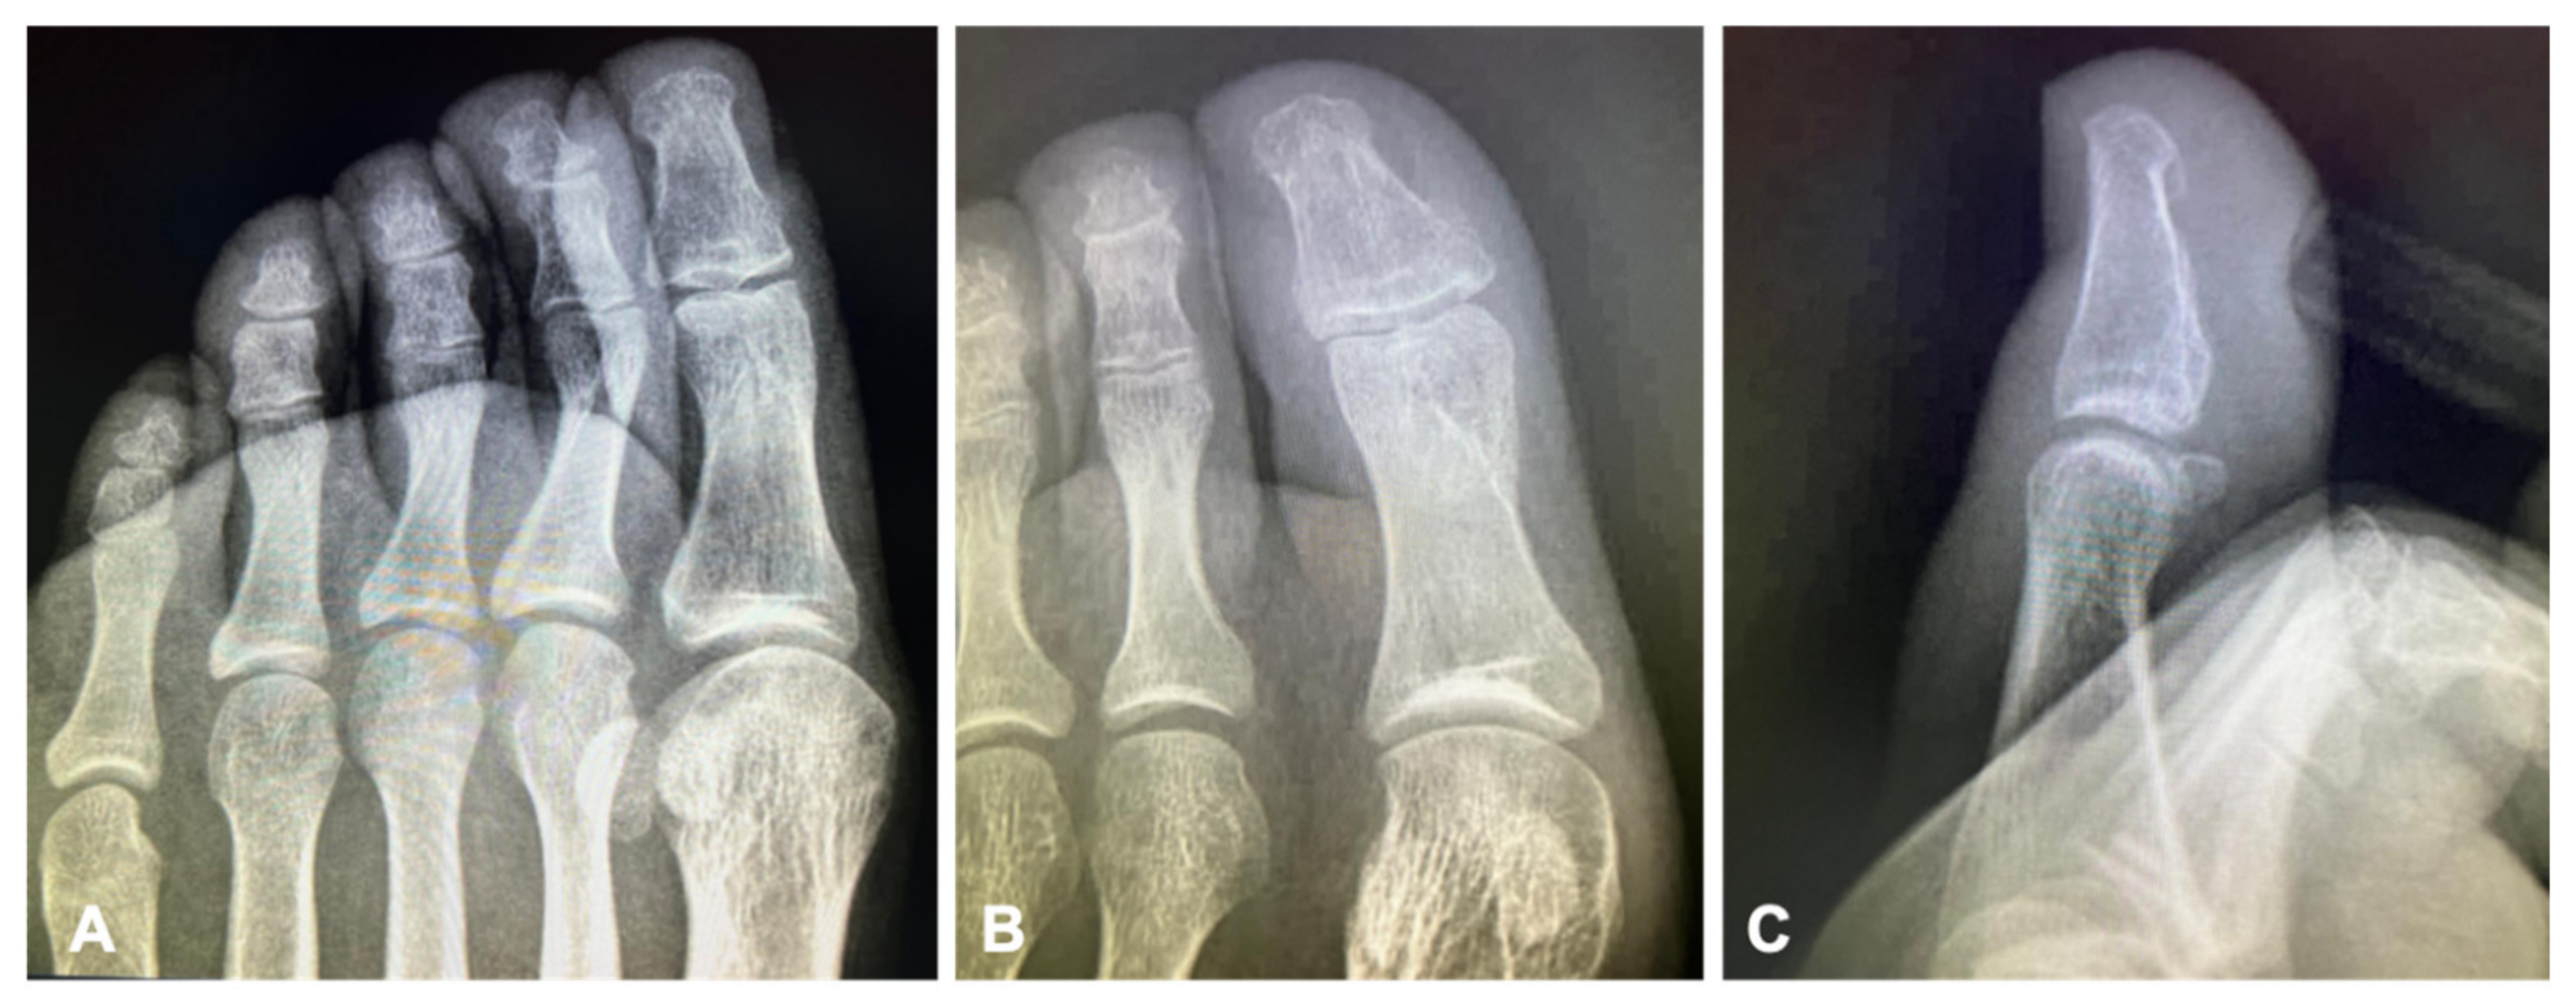

Figure 3), and the patient resumed normal walking and weight bearing with no pain. Control radiographs were also obtained in the third month showing fracture healing (

Figure 4). At the 6-month follow-up, the patient exhibited a full, pain-free range of motion, could perform all daily activities without limitations, and radiographs demonstrated complete healing with no complications (

Figure 5).